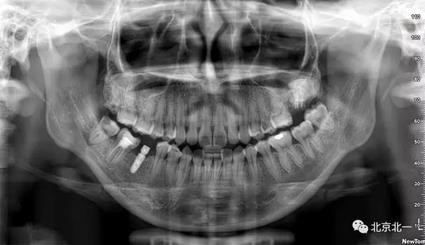

圖二:全景片見27區(qū)高密度影像,考慮智齒埋伏,拍CBCT確認。